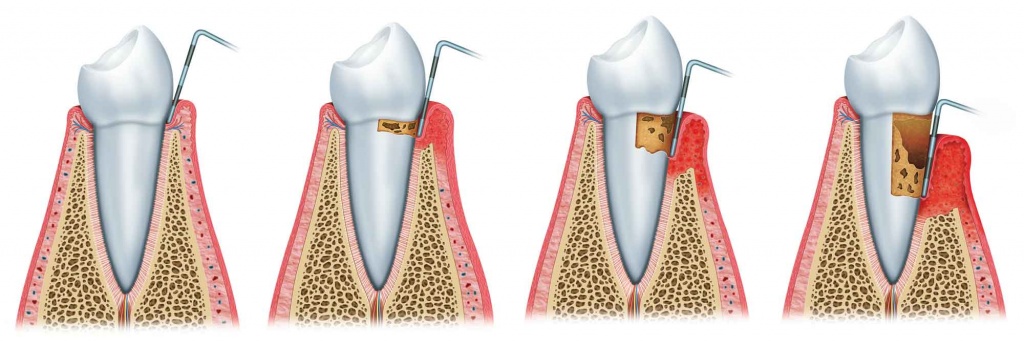

치아 주위 조직의 염증은 진행 정도에 따라 치은염과 치주염으로 나누는 데 잇몸에만 국한된 형태가 치은염, 염증이 잇몸을 넘어 치주인대와 치조골까지 진행된 경우를 치주염이라고 합니다.

치은염이 치주염(풍치)로의 진행과정

치은염의 경우는 일반적인 염증의 증상과 같이 잇몸이 빨갛게 되고 출혈이 있을 수 있는데, 초기에는 칫솔질만 꼼꼼히 해도 어느 정도 회복이 가능하나, 염증이 진행되어 치주염으로까지 진행된 경우에는 계속해서 구취가 나며, 치아와 잇몸 사이에서 고름이 나오고, 저작 시에 불편감이 생기게 됩니다.

이유가 잇몸과 치아 사이에는 틈이 있는데, 이 틈의 잇몸 선 아래 부분을 박테리아가 공격하여 치주인대와 인접조직을 손상 시키게 되고, 염증이 진행되면 더 많은 조직이 파괴되고 홈이 치주낭으로 발전하게 되며, 치주염이 심할수록 치주낭의 길이가 깊어지게 됩니다.